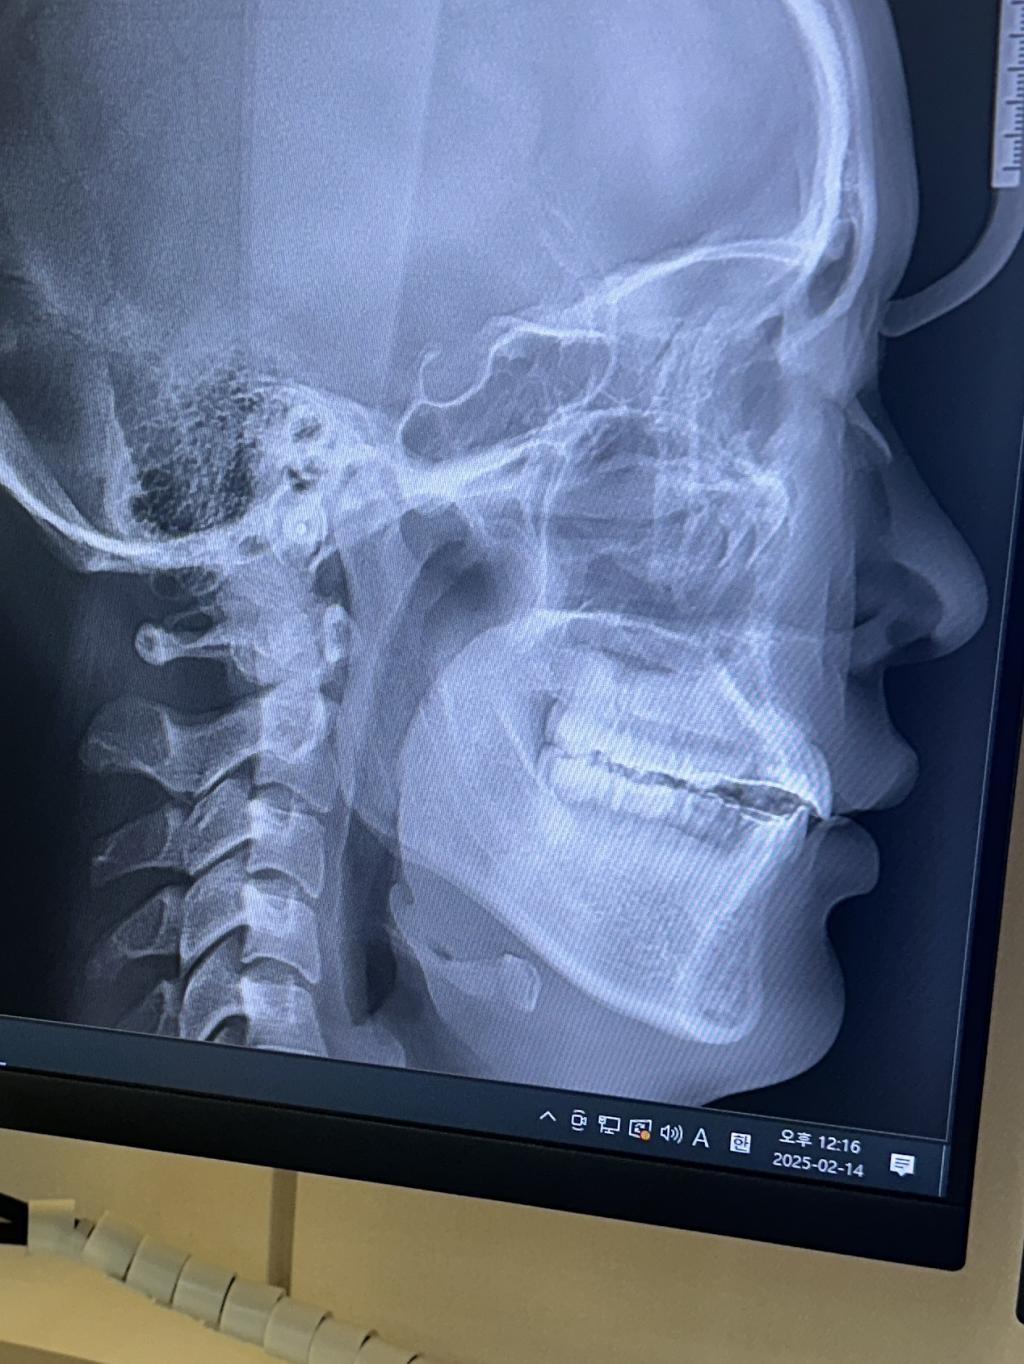

이상적인 상악 앞니의 각도는 95도라고 하는데

저의 상악 앞니의 각도가 115도가 넘어보이시죠..?

완료된 사진입니다,, 앞니가 덜 넣은게 맞는거죠.. 더 넣고싶어요..